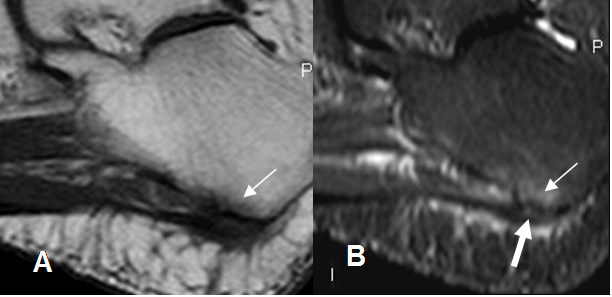

En la RM mide más de 8 mm de espesor, siendo de señal intermedia en T1 e hiperintensa en T2, en su parte proximal. (1). (Fig 115 y 116).

Fig 115. Fasceitis plantar.

A: RM sagital en T1 y B: RM sagital en STIR. Zona hipointensa en T1 e hiperintensa en STIR, sobre la inserción de la fascia por osteítis. (Flecha delgada). Hay área hiperintensa en la fascia, por inflamación o ruptura parcial. (Flecha gruesa).